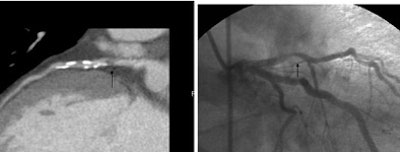

![]() |

| A 59-year-old man presented with classic chest pain symptoms to the ER five days earlier. He was asymptomatic upon presentation to the practice, but opted for an office-based CTA rather than wait three weeks to see a cardiologist. Images top to bottom: Right coronary artery stenosis (arrows) shown on 64-slice CTA at left, cardiac catheterization at right. Next, a normal left circumflex artery (arrows) is depicted on 64-slice CTA at left, cardiac catheterization at right. Next two image sets: Left anterior descending artery stenosis (arrows) is seen on 64-slice CTA at left, cardiac catheterization at right. Bottom image shows excellent outcome on cardiac cath following stenting. |